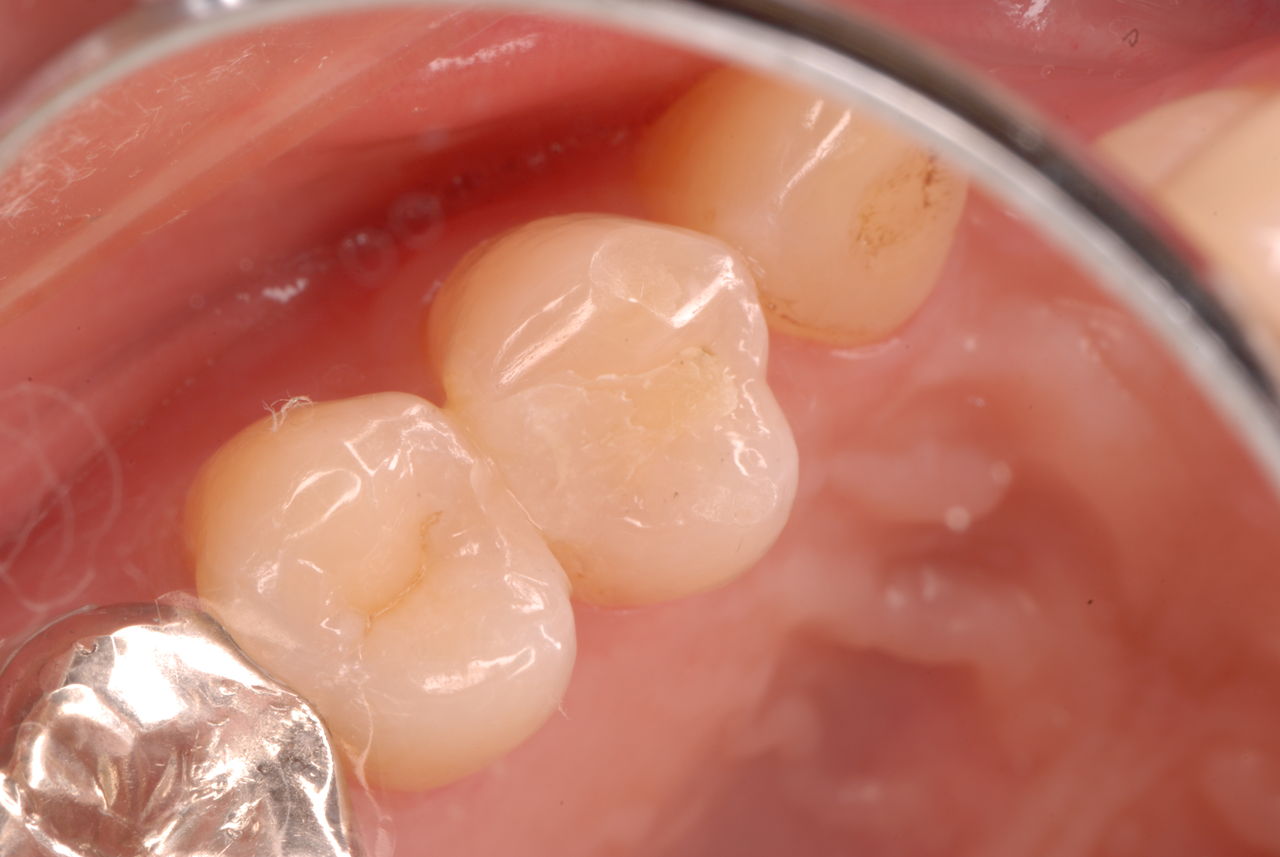

お口の中から差し歯、入れ歯、詰め物を追放しましょう!

口の中の病気を治し、病気を興さない医療を目指します。

二度とお口の中へ変なものを入れなくても済むように

予防に精進いたしましょう!安全な矯正、美容を目指しましょう!